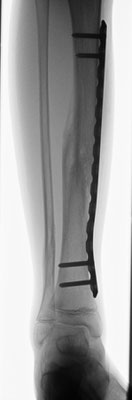

Stark verschobener Unterschenkelbruch bei einem 14- jährigen. Minimal-invasive Stabilisierung mit winkelstabiler Platte. Das Bein kann nach Abklingen der akuten Schwellung bereits wieder mit 15 kg an Gehstützen belastet werden. Volle Belastbarkeit nach 6 – 10 Wochen.